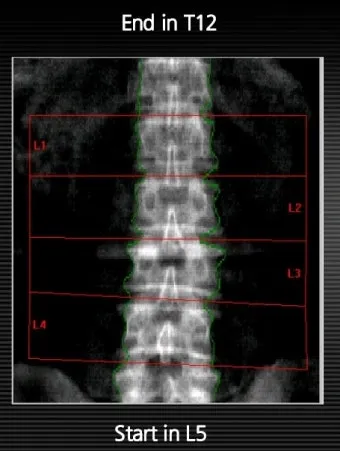

T-score는 30세 젊은 성인의 골밀도와 비교한 값이에요. 이게 가장 중요한 지표라고 할 수 있습니다. 근데 Z-score는 같은 나이, 같은 성별의 평균과 비교한 값이거든요.

예를 들어 60세 여성이 T-score -2.0, Z-score -0.5를 받았다면? T-score로는 골감소증이지만, 같은 나이 또래와 비교하면 평균 수준이라는 의미입니다. 이런 차이를 알고 있으면 결과 해석이 훨씬 쉬워져요.

2025년 최신 가이드라인에 따르면, T-score만으로 치료 여부를 결정하지 않고 개인의 골절 위험도를 종합적으로 평가한다고 하더라고요. 아산병원 골밀도 관리 정보에서도 이런 내용을 확인할 수 있어요.